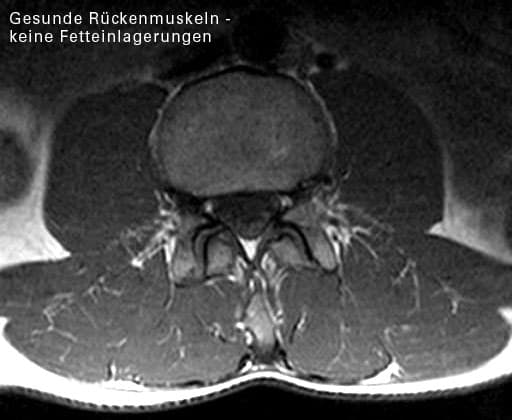

2. Bei chronischen Rückenbeschwerden zeigen die Rückenmuskeln

• einen Schwund von aktivem Muskelgewebe

• eine Umwandlung von Muskeln in Fettgewebe

• eine Umwandlung von Muskeln in Bindegewebe

• eine krankhafte Muskelaktivität

Die hat eine Ulmer Forschergruppe Ende der 90er Jahre nachgewiesen